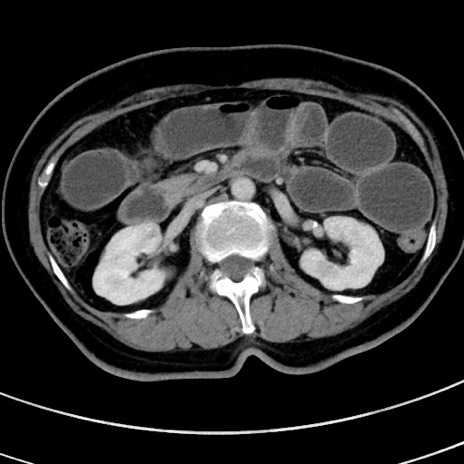

症例9(横断像)

【症例】 60歳代女性

【主訴】むかつき、みぞおちの痛み

【現病歴】3日前よりむかつきがあり、食事がとれない。

【既往歴】糖尿病

【身体所見】発熱なし、心窩部圧痛軽度あるも、腹膜刺激症状なし。

【データ】WBC 7400、CRP 1.92